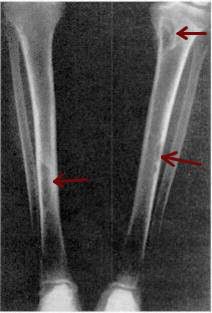

Osteitis fibrosa cystica (OFC) is a skeletal disorder caused by an overproduction of parathyroid hormone from the overactive parathyroid glands. Osteitis fibrosa cystica is the late manifestation of the hyperparathyroidism. The incidence of bone lesions has decreased from 80% in the past to 15% in the present. Symptoms are due to bone softening and hypercalcemia, which might include bone mass or fractures, kidney stones, peptic ulcer, weight loss, nausea, loss of appetite, psychic moans, and abdominal groans.